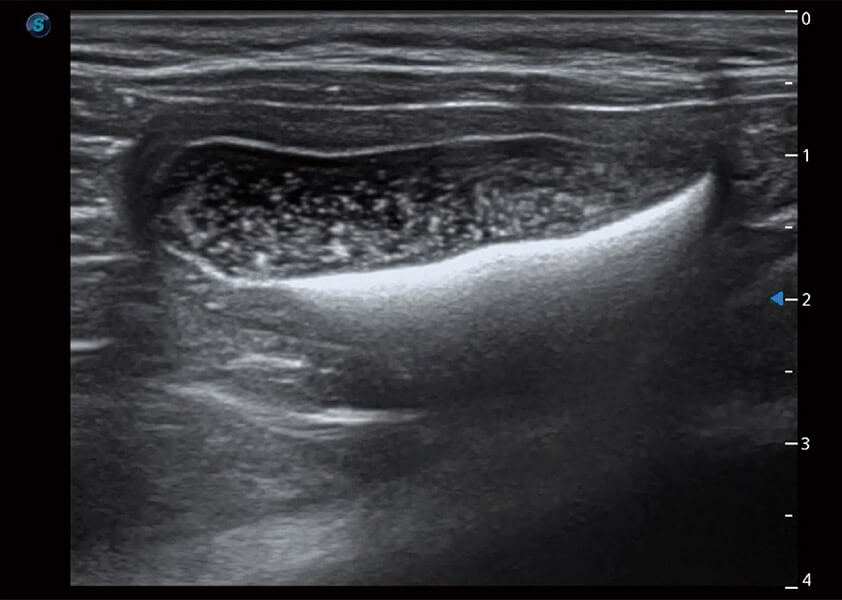

ProPet 60 作为一款高端台式动物超声设备,为动物医生的日常诊断提供了一系列贴合动物临床需求、解决临床实际问题的高级成像功能。凭借全系列高清探头,满足医生对腹部、心脏、生殖、浅表、肌骨等成像的所有需求,切实帮助您提升检查效率,提高诊断信心。

动物是人类最亲密的朋友和最值得信赖的伙伴。竞技宝(JJB)官方网站也一直致力于探索动物专用的超声影像解决方案。 全新推出的ProPet系列,是竞技宝(JJB)官方网站在动物超声影像智能化、专业化、精准化的一次跨越式革新。动物不能用言语来表述自己的不适,通过超声影像,ProPet系列搭建了动物医生与不同物种沟通的“桥梁”,为动物医生注入了“治愈之力”。